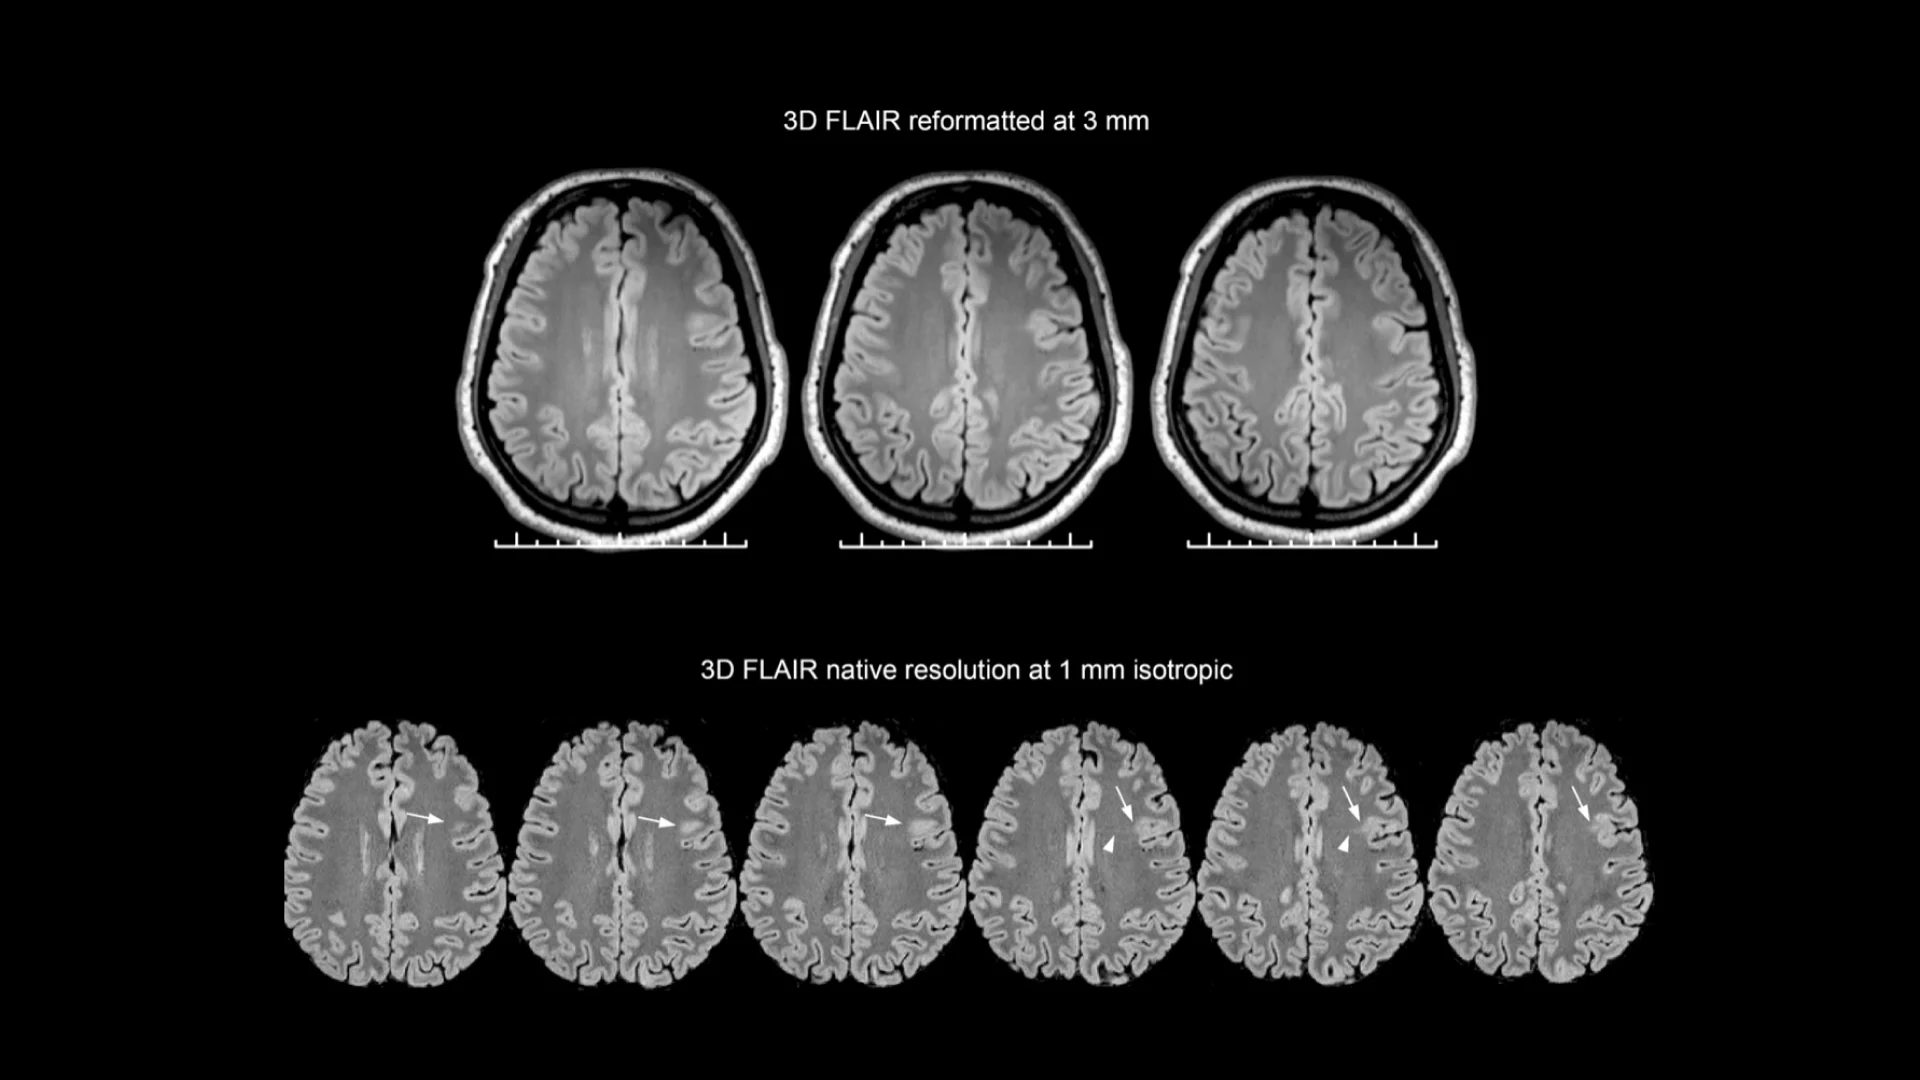

Processing. Multi-modal MRI standardization and quality control form the open-source foundation available for research use

Analysis. Whole-brain morphometric mapping reveals deviation patterns across cortical and subcortical structures

Diagnostics. AI-powered lesion identification combined with expert radiologist validation delivers comprehensive case reports